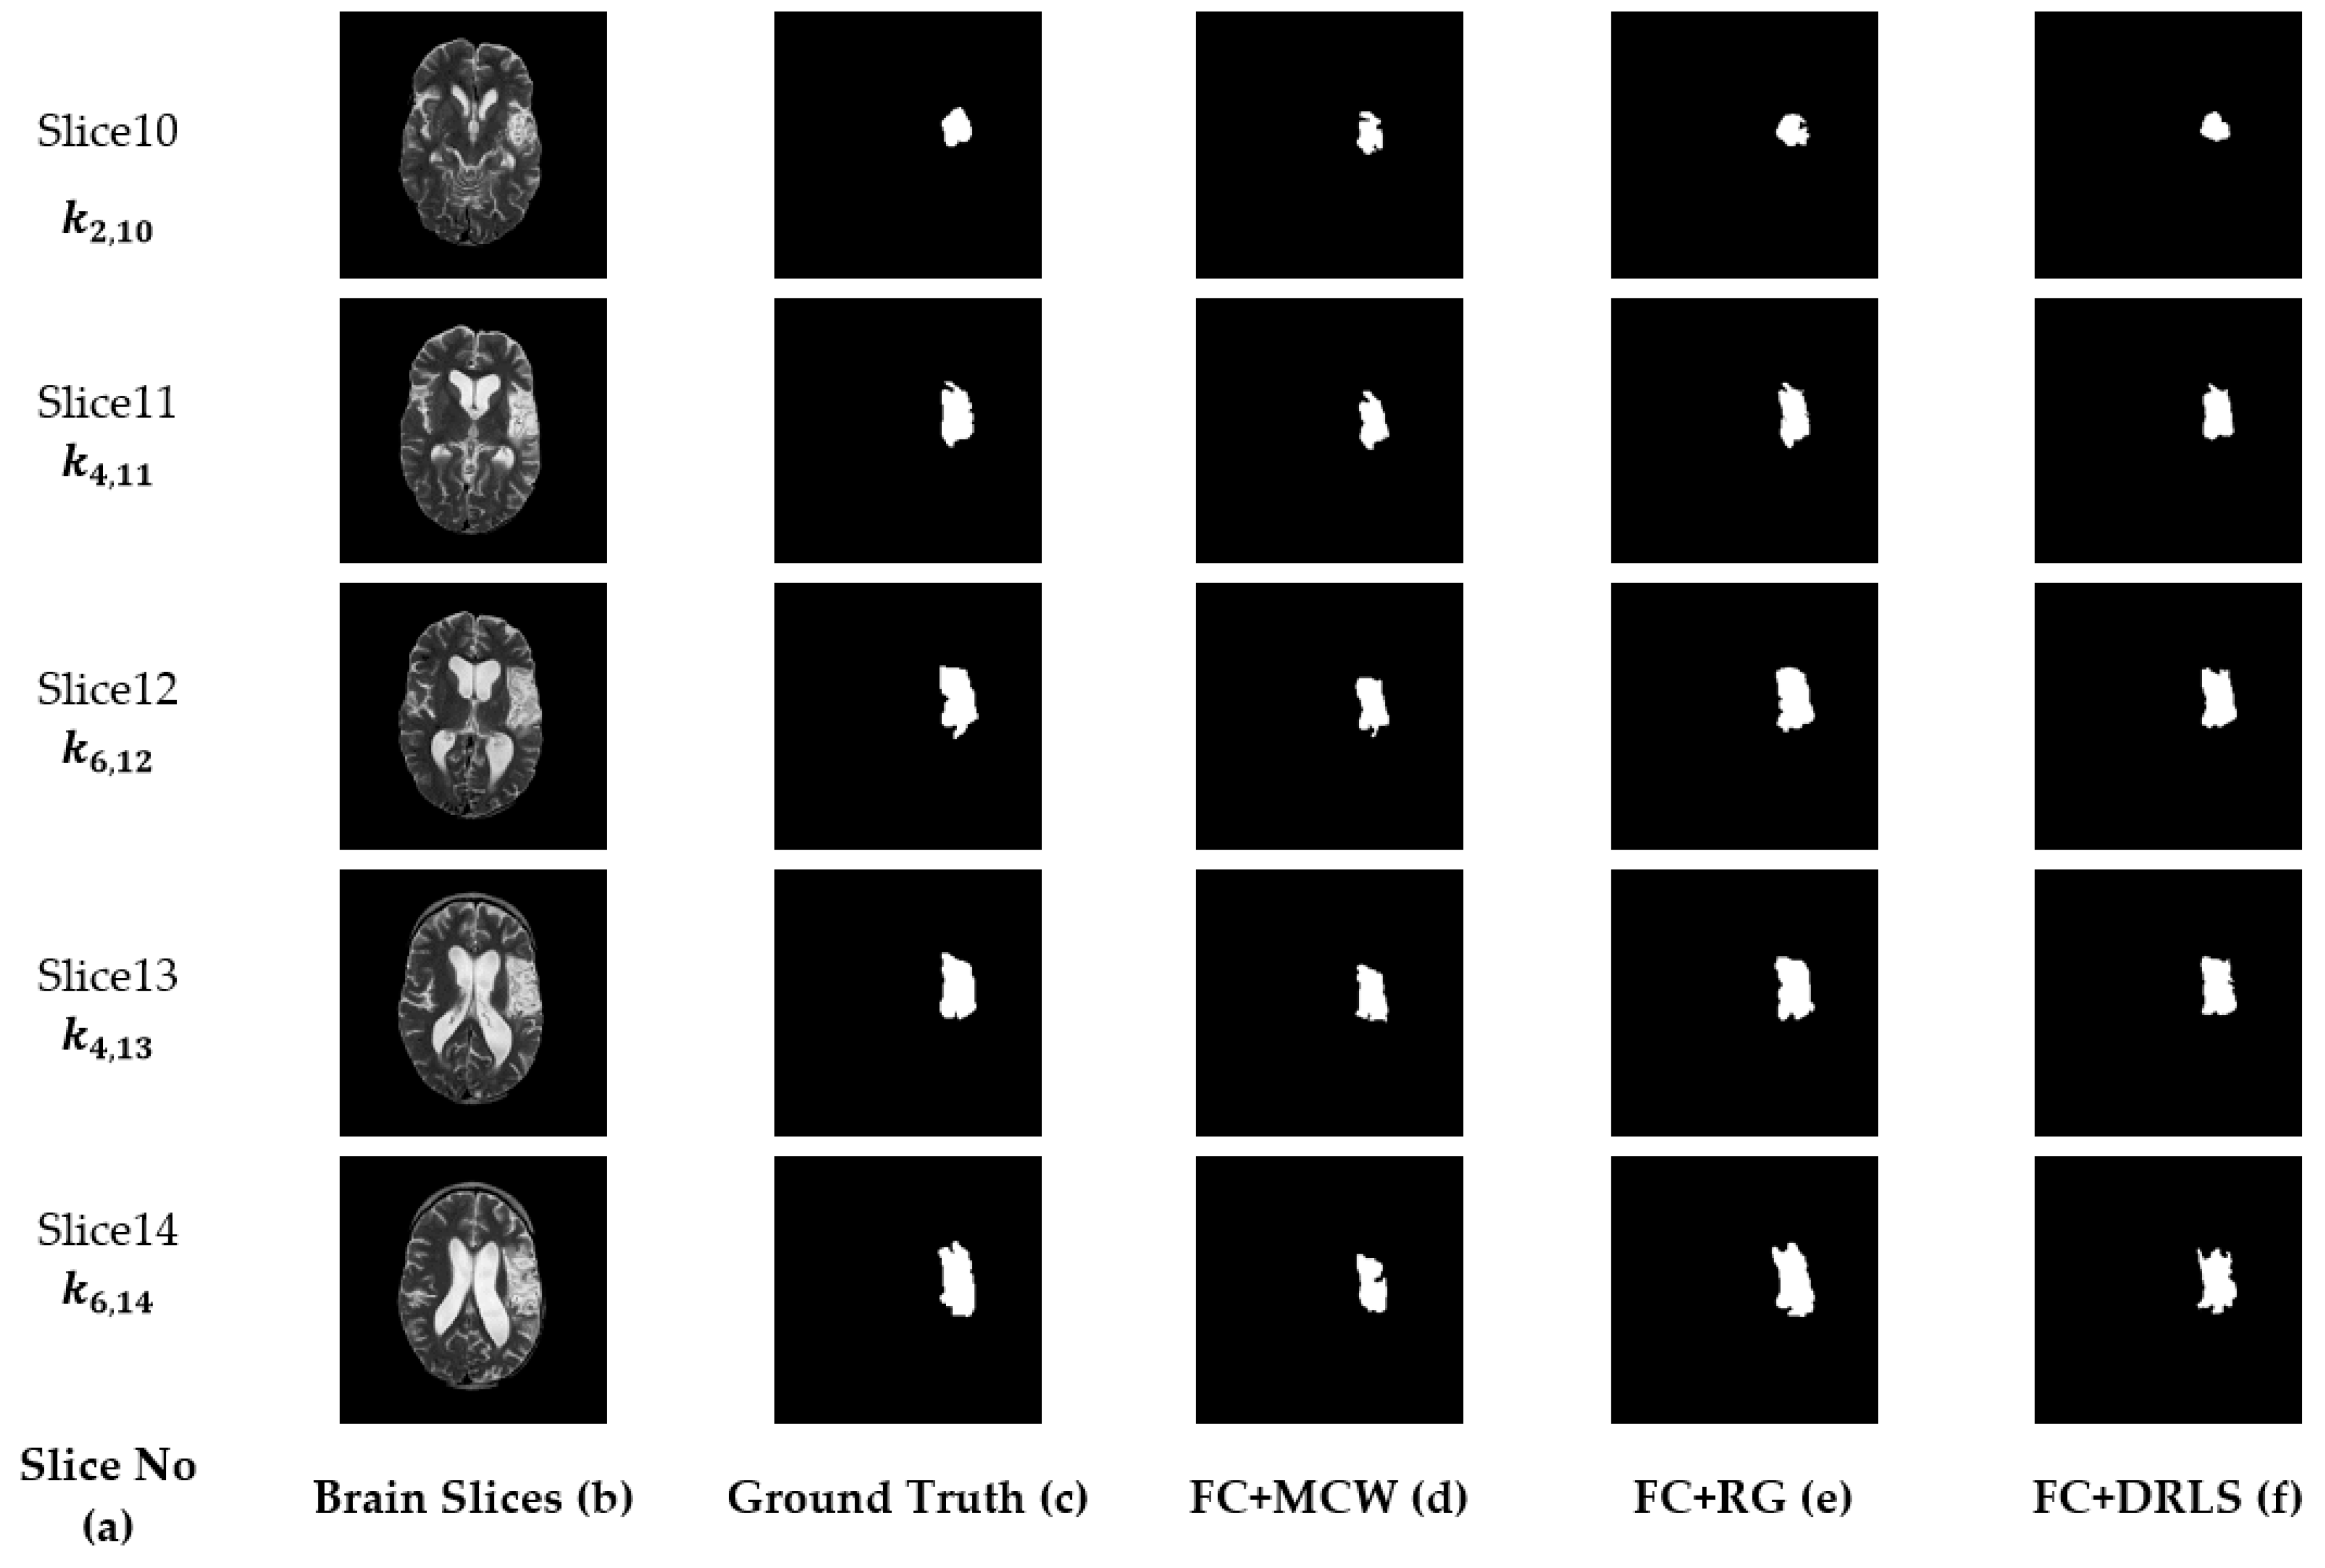

| Slice | Jaccard | Dice | FPR | FNR | |

|---|---|---|---|---|---|

| FC+MCW | S10 | 0.6932 | 0.7832 | 0.1027 | 0.0612 |

| S11 | 0.8223 | 0.8828 | 0.1075 | 0.0311 | |

| S12 | 0.8185 | 0.8569 | 0.1579 | 0.0424 | |

| S13 | 0.8137 | 0.8761 | 0.1683 | 0.0422 | |

| S14 | 0.7314 | 0.8168 | 0.1544 | 0.1201 | |

| FC+RG | S10 | 0.7209 | 0.7767 | 0.1123 | 0.0723 |

| S11 | 0.8149 | 0.8934 | 0.1099 | 0.0793 | |

| S12 | 0.7953 | 0.8491 | 0.1184 | 0.0683 | |

| S13 | 0.8054 | 0.7962 | 0.1163 | 0.0923 | |

| S14 | 0.7821 | 0.8021 | 0.1201 | 0.0876 | |

| FC+DRLS | S10 | 0.6874 | 0.7949 | 0.1336 | 0.0642 |

| S11 | 0.8104 | 0.8972 | 0.1253 | 0.032 | |

| S12 | 0.8256 | 0.8625 | 0.1368 | 0.0296 | |

| S13 | 0.8179 | 0.8879 | 0.1374 | 0.038 | |

| S14 | 0.7555 | 0.8596 | 0.1164 | 0.0958 |